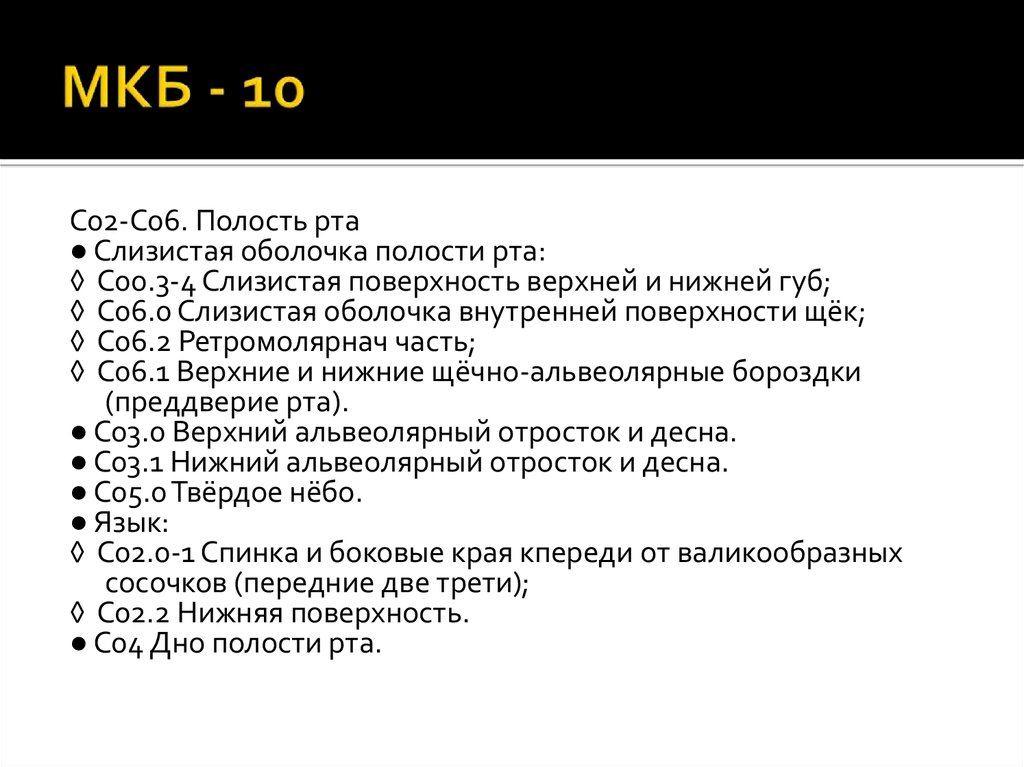

Код мкб 10 атерома головы

Код мкб 10 атерома головы 109 фото